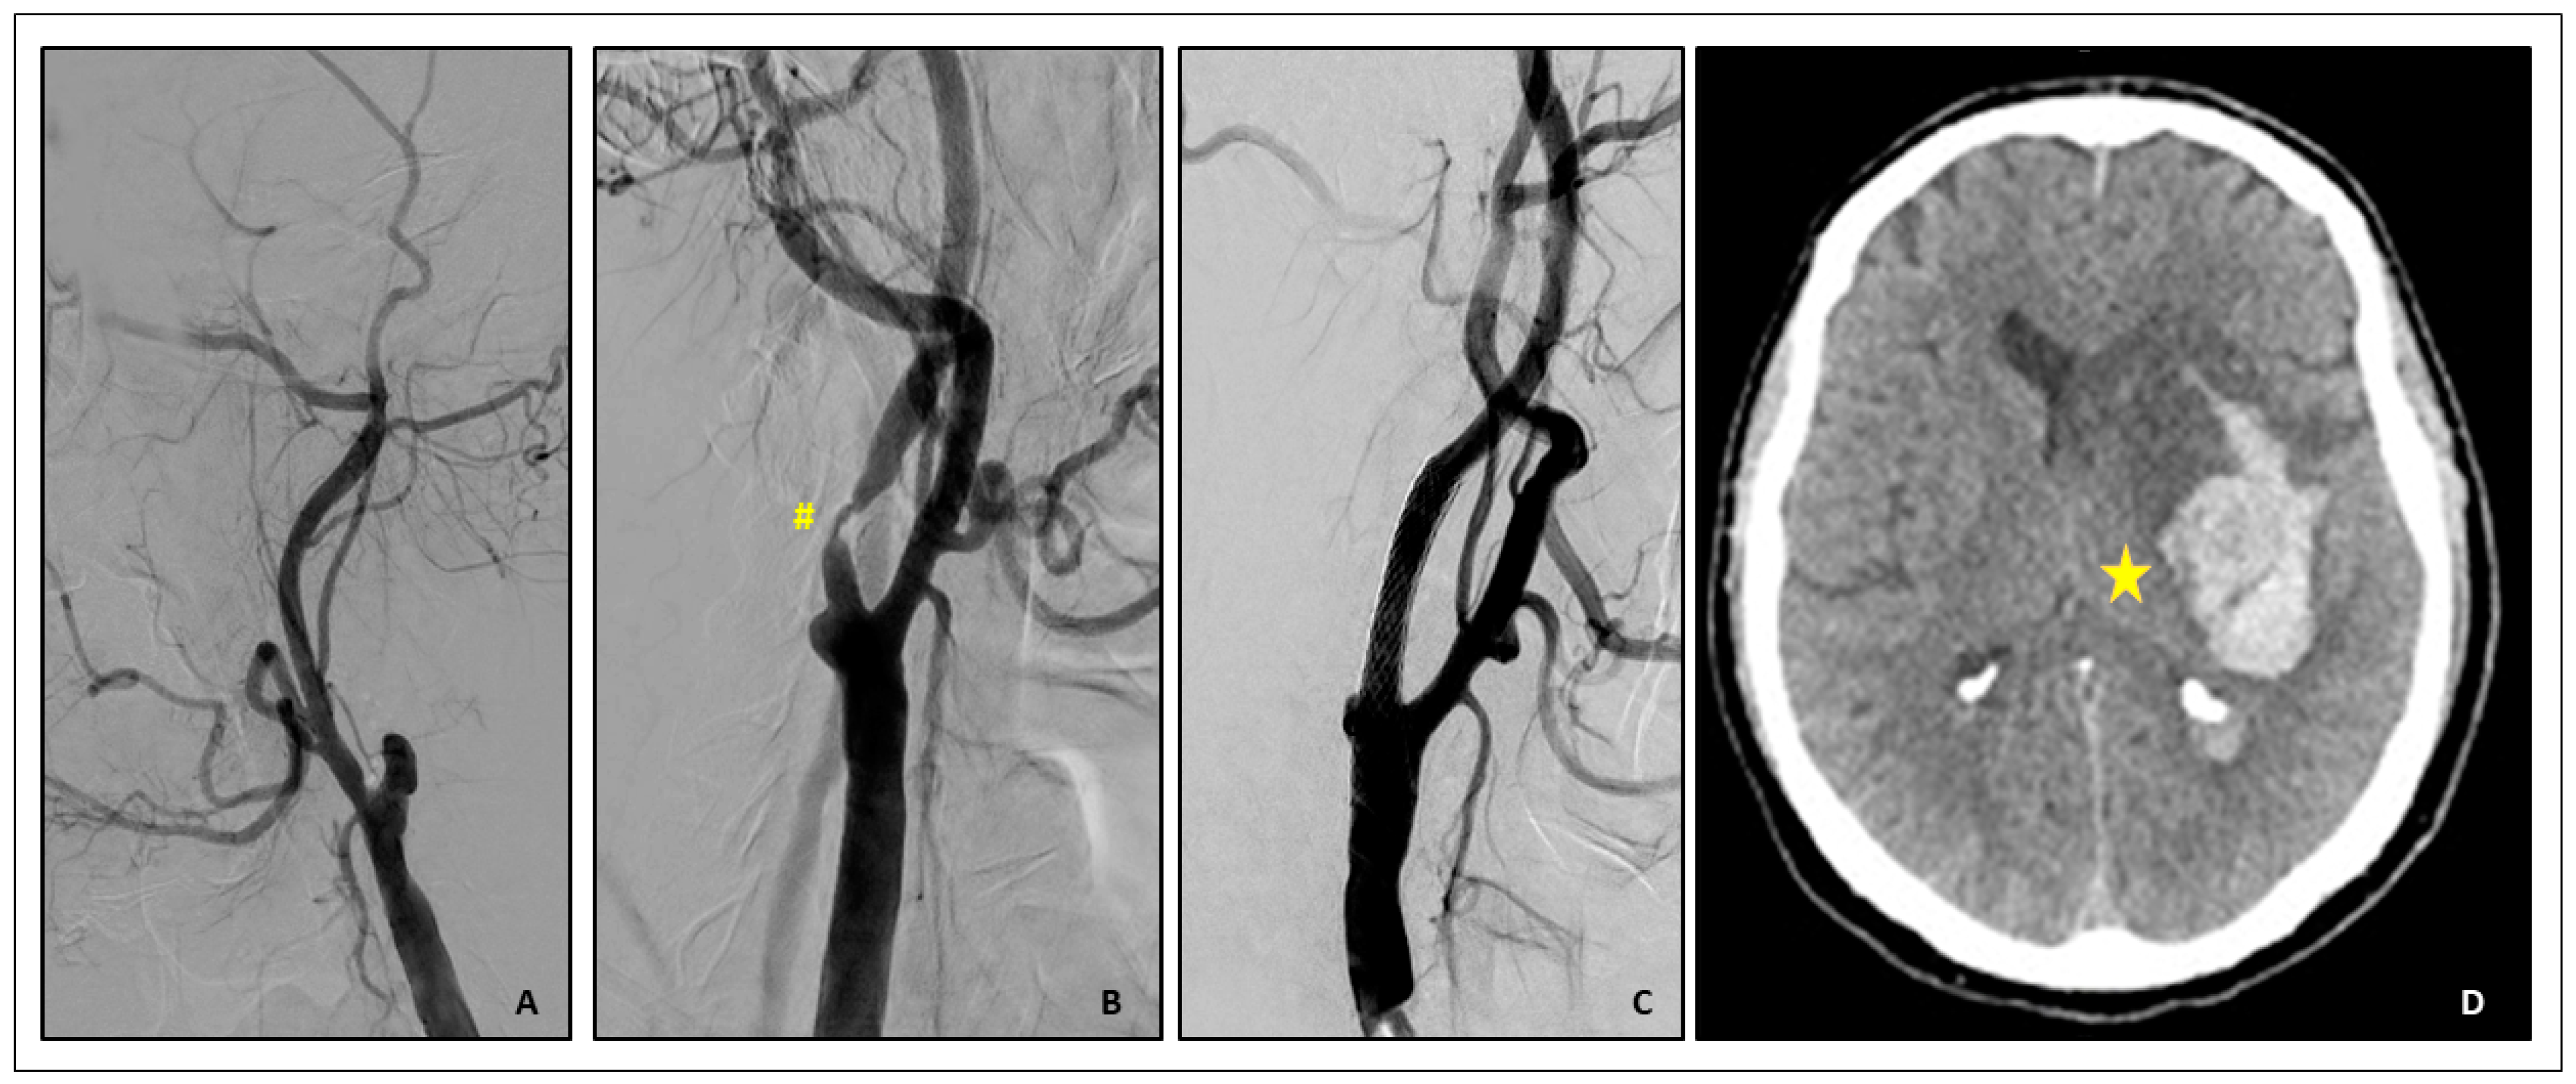

- Cerebral hyperperfusion syndrome (CHS)

- Brief case description